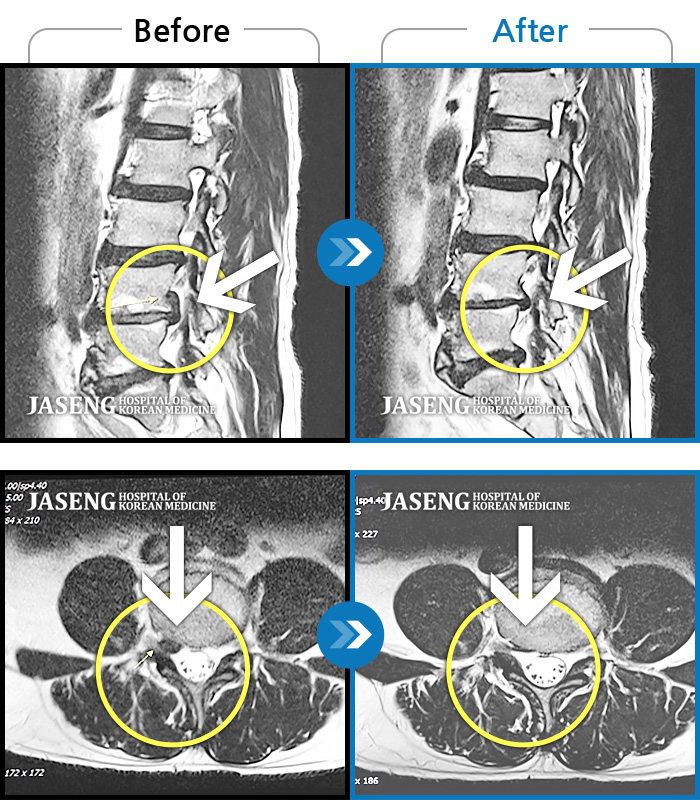

Before

After

환자에게 사전 동의를 받아 동일 조건에서 촬영되었습니다.

개인에 따라 치료 후 부작용이 발생할 수 있으니 의료진과 상담 후 치료를 진행하시기 바랍니다.

엉치 통증 및 우측 종아리 후면 통증

허리 중간부위 통증, 간헐적으로 양측 엉치 부위 저림